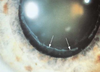

This patient c/o glare and vague shadow (double) image. Cause of this problem?

Capsular rupture

Association explains patient’s disorder for abnormality shown

anterior subcapsular cataract a/w atopic dermatitis

cataract formation in 25% (2nd and 3rd decade) resemble shield like plaques